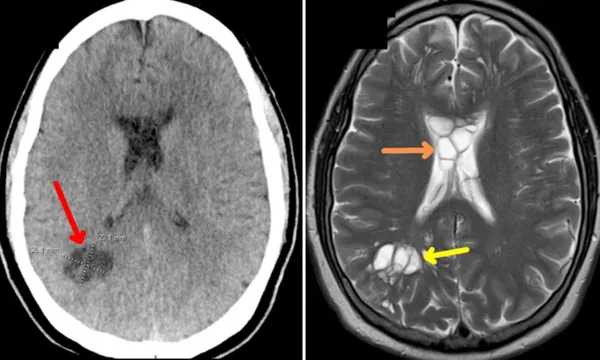

Trong trường hợp này, cùng với tình trạng sưng tấy, bệnh nhân còn phát triển các u nang ở cả hai bên não. Điều này sau đó được xác định là do sán dây đã đẻ trứng trong não người đàn ông.